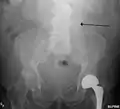

An abdominal aortic aneurysm is usually diagnosed by physical exam, abdominal ultrasound, or CT scan. Plain abdominal radiographs may show the outline of an aneurysm when its walls are calcified. However, the outline will be visible by X-ray in less than half of all aneurysms. Ultrasonography is used to screen for aneurysms and to determine their size if present. Additionally, free peritoneal fluid can be detected. It is noninvasive and sensitive, but the presence of bowel gas or obesity may limit its usefulness. CT scan has nearly 100% sensitivity for an aneurysm and is also useful in preoperative planning, detailing the anatomy and possibility for endovascular repair. In the case of suspected rupture, it can also reliably detect retroperitoneal fluid. Alternative less often used methods for visualization of an aneurysm include MRI and angiography.

The faint outline of the calcified wall of an AAA as seen on plain X-ray